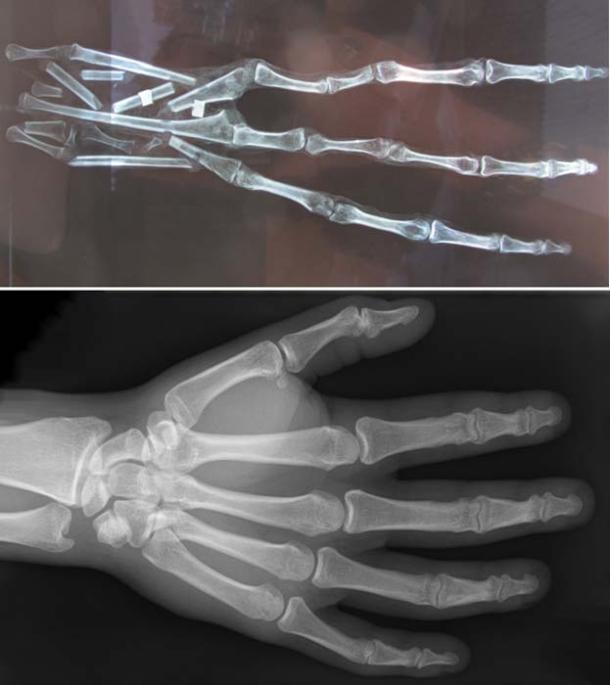

Brien Foerster took the hand and skull to physicians in Cusco, Peru, who did not wish to be identified. The hand was x-rayed and found to have 6 bones in each finger, while a regular human hand has 3 bones. The examination revealed that the mummified hand is made up of bone and skin, suggesting that it is not a fake (unless it was somehow made using real bones, flesh and skin).

Top: X-ray of the 3-fingered hand, showing 6 bones in each finger. Credit: Brien Foerster / Hidden Inca Tours. Bottom: X-ray of a human hand, showing 3 bones in each finger. (CC by SA 3.0)